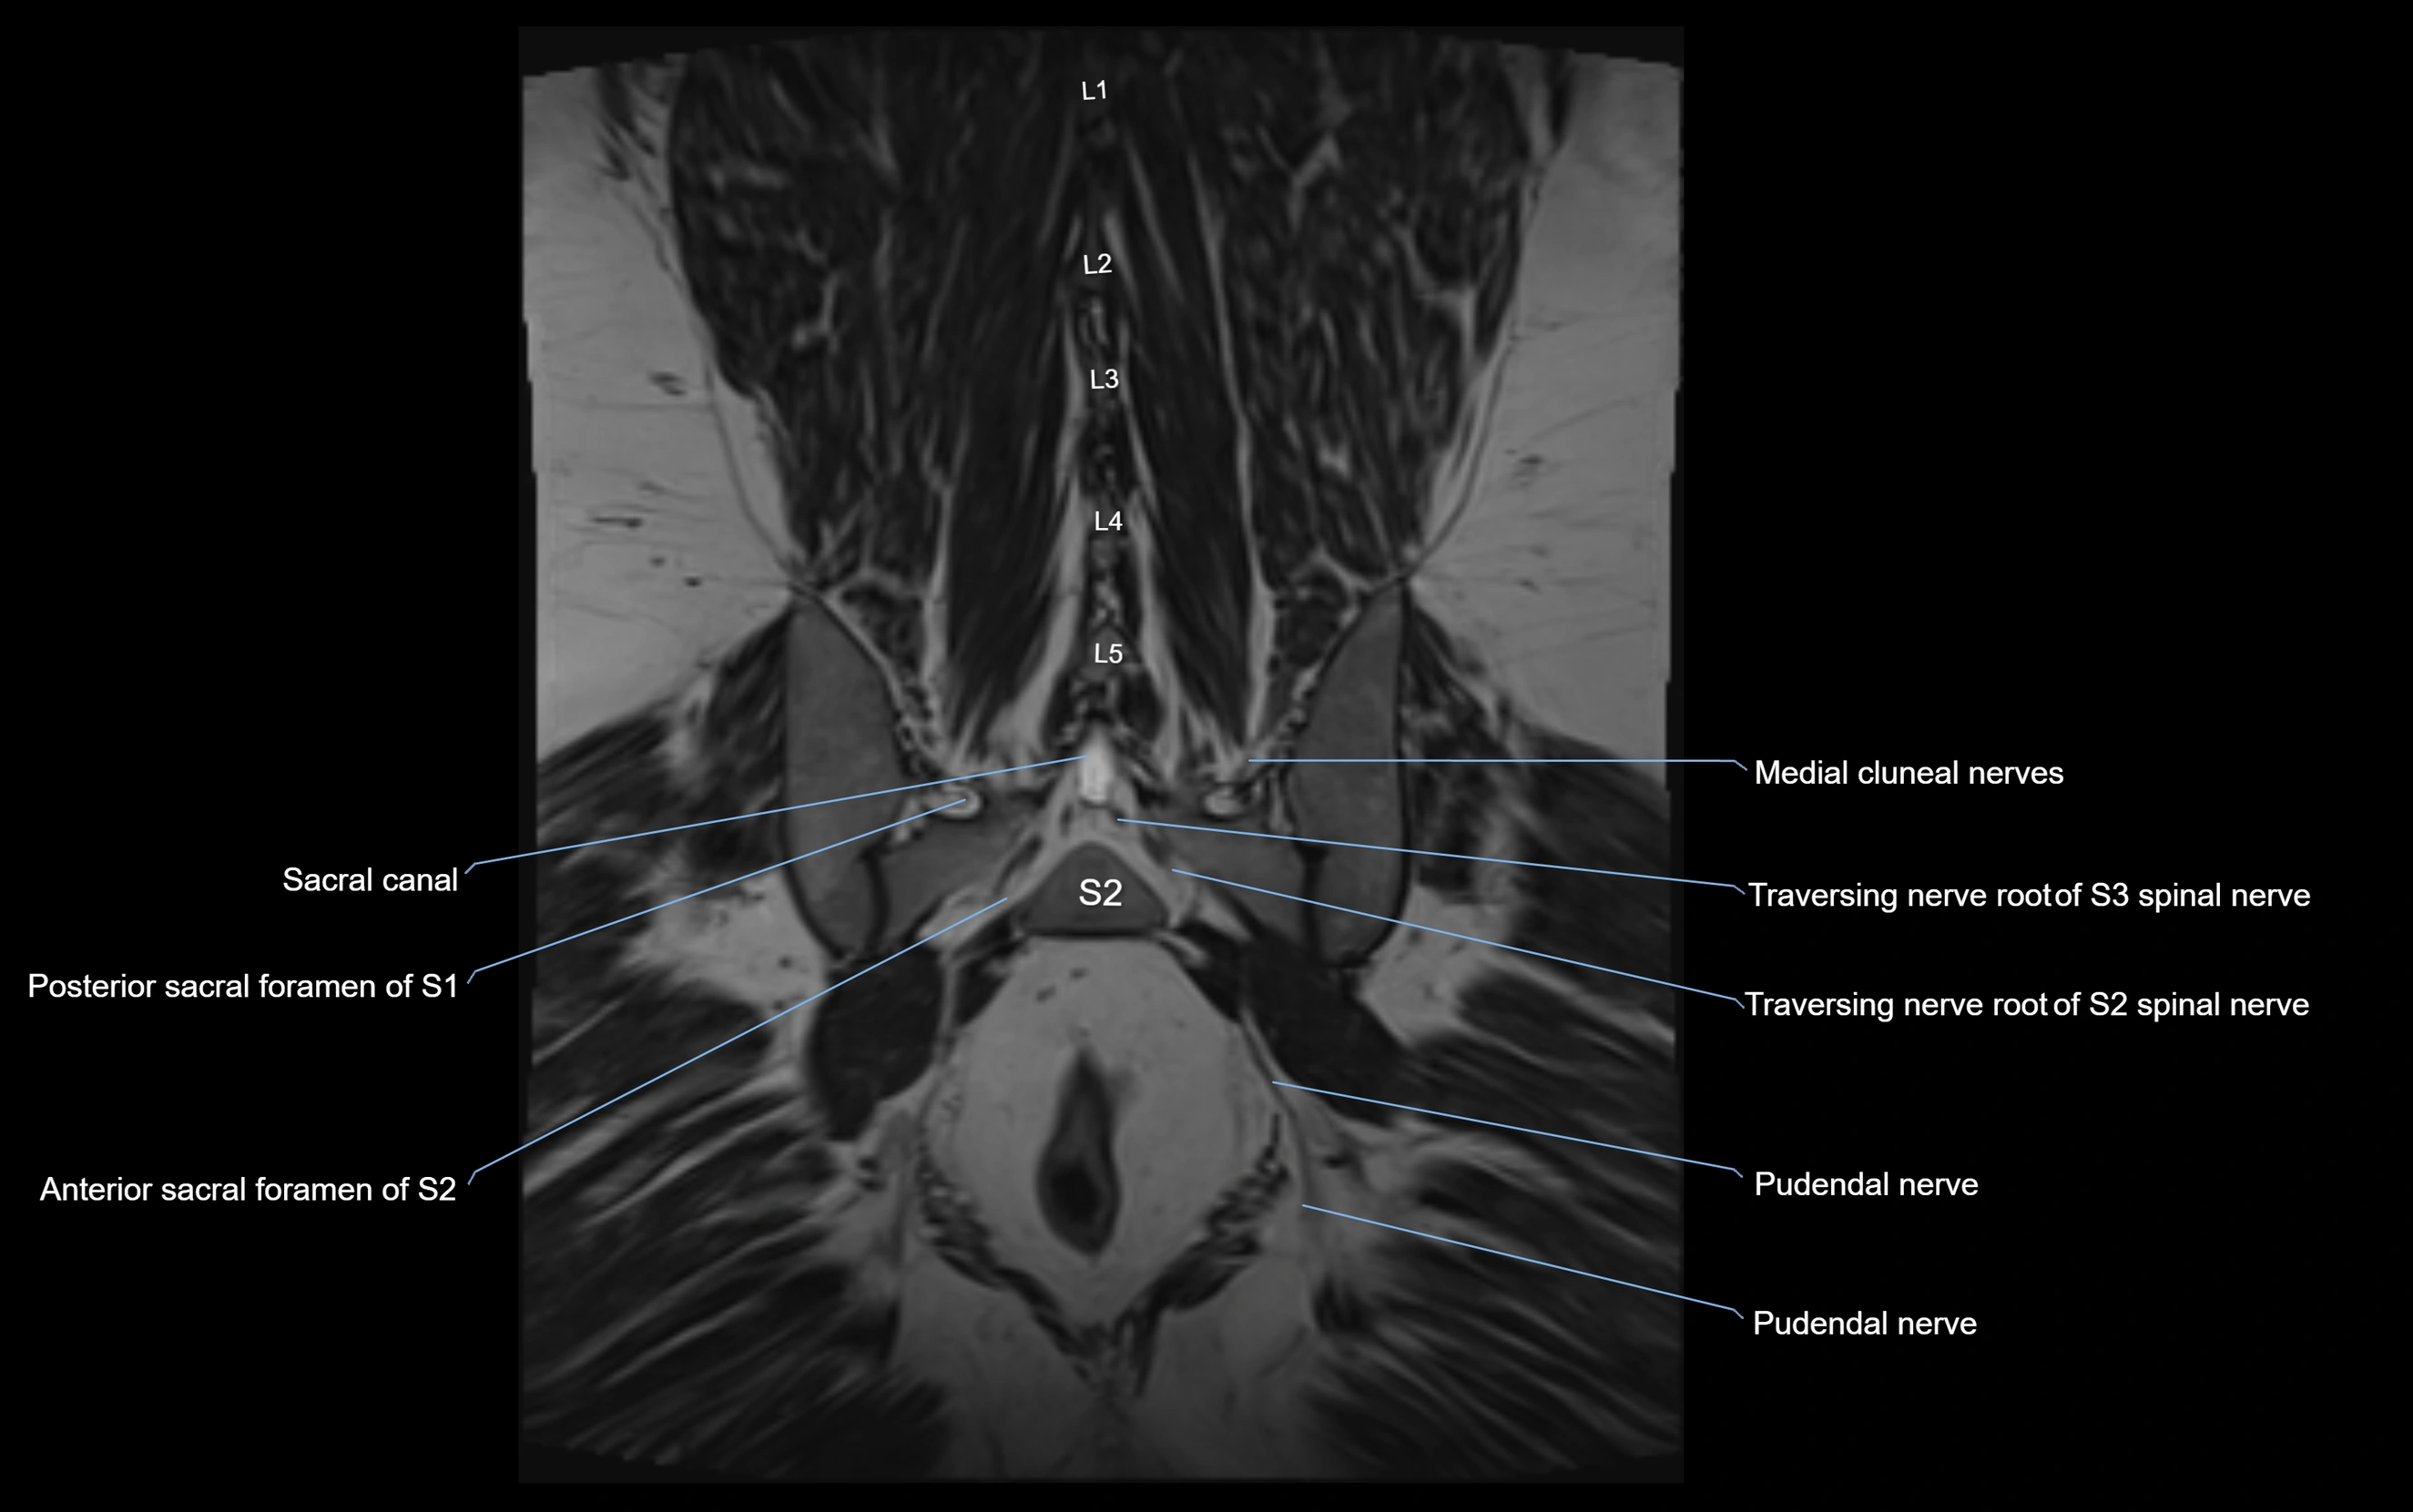

MRI Appearance

T1-weighted images:

• Nerve appears as a very thin low-to-intermediate signal intensity structure

• Surrounded by bright fat, aiding visualization

T2-weighted images:

• Nerve shows intermediate to mildly hyperintense signal compared to muscle

• Pathological involvement appears brighter

STIR (Short Tau Inversion Recovery):

• Normal nerve appears dark

• Inflamed or entrapped nerve appears bright hyperintense

T1 Fat-Sat Post-Contrast:

• Normal nerve enhances minimally

• Pathologic nerve (neuritis, entrapment, tumor infiltration) shows focal or diffuse enhancement

3D T2 SPACE / CISS:

• Nerve appears intermediate to mildly hyperintense compared to muscle

• Surrounded by bright fat or CSF, improving visualization

• Best sequence for mapping small pelvic nerves such as the anococcygeal